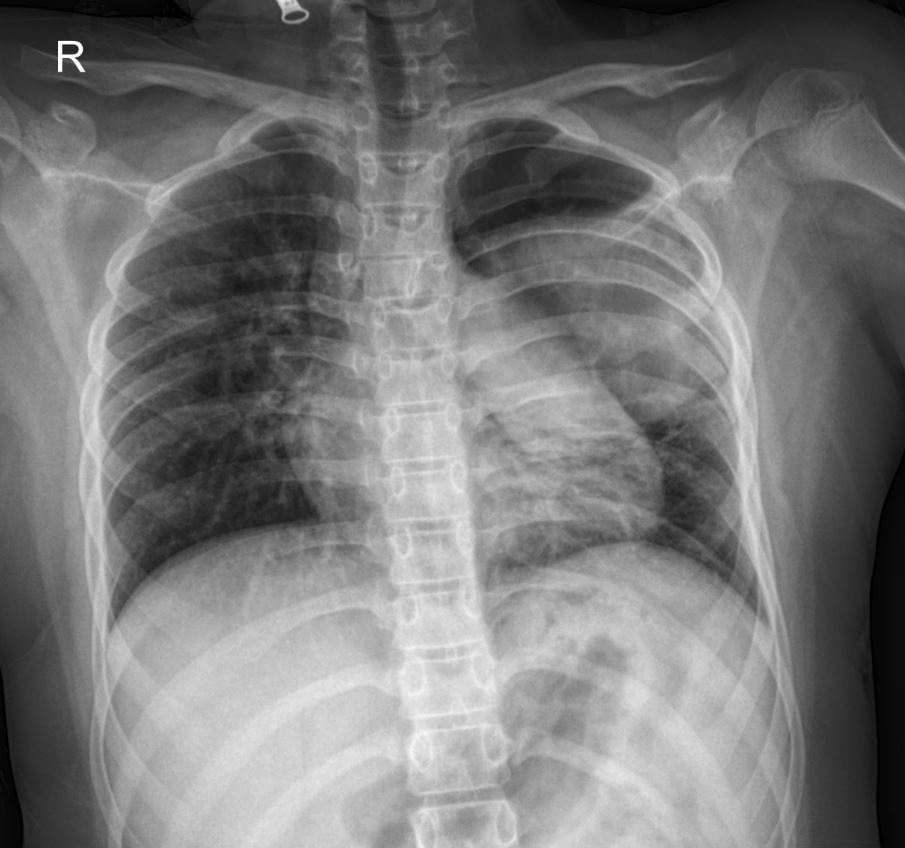

Radiological Findings (Initial PA Chest X-ray):

The initial posteroanterior (PA) chest X-ray image provided offers a critical first look. Observe the left hemithorax, particularly the upper lobe. A large, ill-defined lucency with surrounding consolidation is evident. This appearance strongly suggests a cavitary lesion, an important finding that immediately raises the differential diagnoses of lung abscess, tuberculosis, or even less common etiologies in this age group. The significant size of the lesion is also notable, prompting urgent further investigation.

This case highlights the importance of integrating clinical presentation, past medical history, and multi-modal imaging in diagnosing complex lung pathologies in children. The large cavitary lesion seen on the X-ray and confirmed by CT demands a thorough workup to differentiate between infectious etiologies like lung abscess (bacterial) and tuberculosis, especially given the patient’s previous severe pneumonia. The history of right-sided disease at 5 years of age and current left-sided involvement prompts consideration of underlying conditions that may predispose to recurrent or persistent lung pathology.

The chest X-ray in this case serves as a crucial initial imaging modality, clearly demonstrating a significant cavitary lesion in the left upper lobe. This finding, combined with the patient’s symptoms and history, guides the subsequent diagnostic and therapeutic steps. Further investigations are underway to pinpoint the exact etiology of this complex lung lesion.